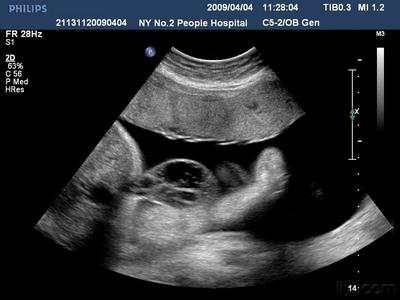

据介绍,经过中山大学法医鉴定中心鉴定,根据法医系统尸体解剖检验,邹某之女体表及内部器官未发现机械性损伤征象,故可排除机械性暴力作用致死。结合案情分析,邹某之女属未成熟儿,符合宫内窒息死亡。

庭审过程中,原告医生吕某某表示,其和被告邹某此前不认识,并没有任何冤仇,不可能故意对其腹中胎儿进行敲打,其只是进行了正常的检查操作。此外,其对邹某检查时,发现邹某身体某些指标显示异常,这些都可能对胎儿的发育造成影响。

被告的辩护律师表示,在检查的时候,医生对邹某腹中胎儿敲打了两三下,当时邹某就觉得腹中疼痛,但是并不敢吭声,此后就出现了异常导致腹中胎儿死亡。

对此,原告方则反驳,根据中山大学法医鉴定中心的医学鉴定显示,邹某之女的尸体体表及内部器官未发现机械性损伤征象,故可排除机械性暴力作用致死,因此可以排除与医生操作有关。不过,邹某的辩护人则认为,医学鉴定只是说排除机械性暴力作用致死,并不能排除与医生吕某某的操作有关。